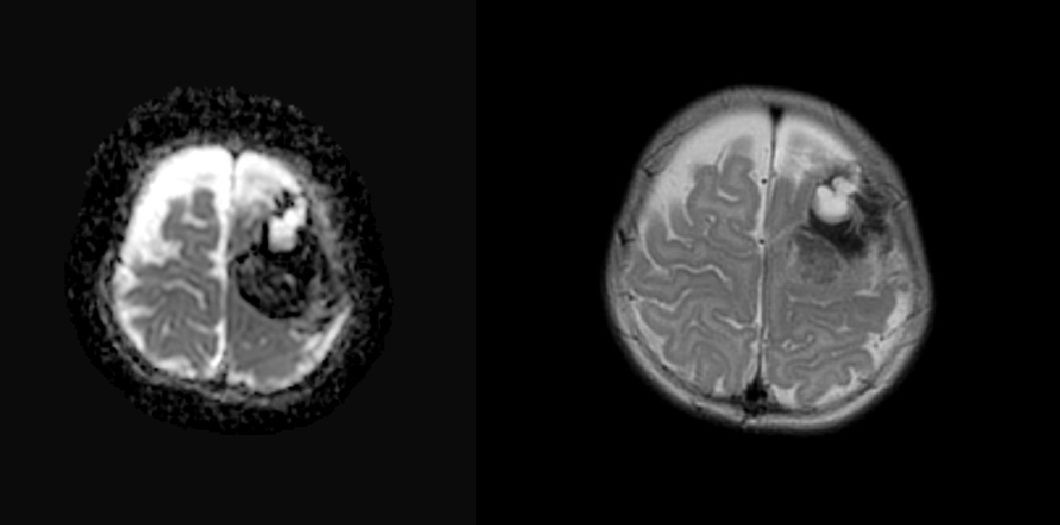

A su llegada, habían cedido los movimientos, las constantes eran normales y a la exploración física destacaba una monoparesia e hipotonía de miembro superior derecho. Se realizó una analítica sanguínea con hemograma y bioquímica normales, un electroencefalograma con actividad eléctrica del hemisferio izquierdo en relación con un posible periodo posictal. Se decide ingreso, administración de bolo intravenoso de Levetiracetam y se pauta mantenimiento con el mismo fármaco. Ante persistencia de focalidad neurológica con ausencia de prensión palmar derecha se realiza una resonancia magnética cerebral (Fig. 1) con presencia de una hemorragia a nivel frontoparietal izquierda en la que se sospecha base tumoral, por lo que se remite a hospital de referencia.

Figura 1. Imagen de resonancia magnética cerebral al ingreso

La hemorragia intracraneal puede ocurrir a cualquier edad, espontáneamente o tras un traumatismo, y es una de las complicaciones más graves, con una mortalidad que alcanza el 20%. La clínica es inespecífica y especialmente difícil de identificar en lactantes, suele incluir vómitos, irritabilidad (por la cefalea) y letargia, aunque en ocasiones la hemorragia es silente y solo detectable por neuroimagen. En este caso, dado que el sangrado fue próximo a la corteza cerebral, se manifestó como crisis epilépticas parciales y persistencia posterior de focalidad neurológica.